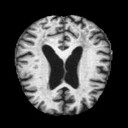

Alzheimer's disease is one of the most common diseases in the world and detecting the onset of the disease is very important to get the proper treatment and diagnostics for the disease.

The CNN model predicts patterns into the images and classifies the different forms of dementia. class 1 = Mildly demented, class 2 = moderately demented, class 3 = non-demented, class 4 = very mildly demented